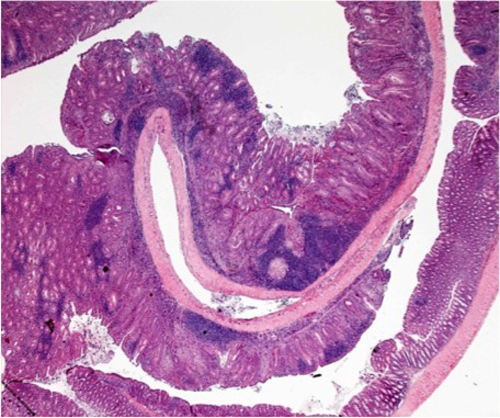

Una de les associacions millor documentades entre inflamació crònica i tumorogènesi és dóna en el càncer colorectal de pacients que pateixen inflamació de l’intestí.

El càncer colorectal és el tercer més comú al món. Els pacients amb la malaltia d’inflamació d’intestí, ja sigui per colitis ulceroses o per colitis de Crohn, tenen un risc més elevat de desenvolupar aquest tipus de càncer.

En un article recent, l’equip d’Àngel R. Nebreda descriu com p38α és fonamental pel manteniment de la bona salut de l’epiteli intestinal, controla la severitat de les colitis i actua de supressor de tumors al còlon.

L’objectiu principal d’aquest projecte és investigar com p38α regula la tumorogènesi colorectal associada a colitis. Els resultats permetran entendre el paper de p38α i els seus efectors en la biologia del càncer, així com la interacció entre les cèl·lules epitelials i del teixit, per tal d’estimar el seu valor com a diana terapèutica o marcador de diagnòstic.